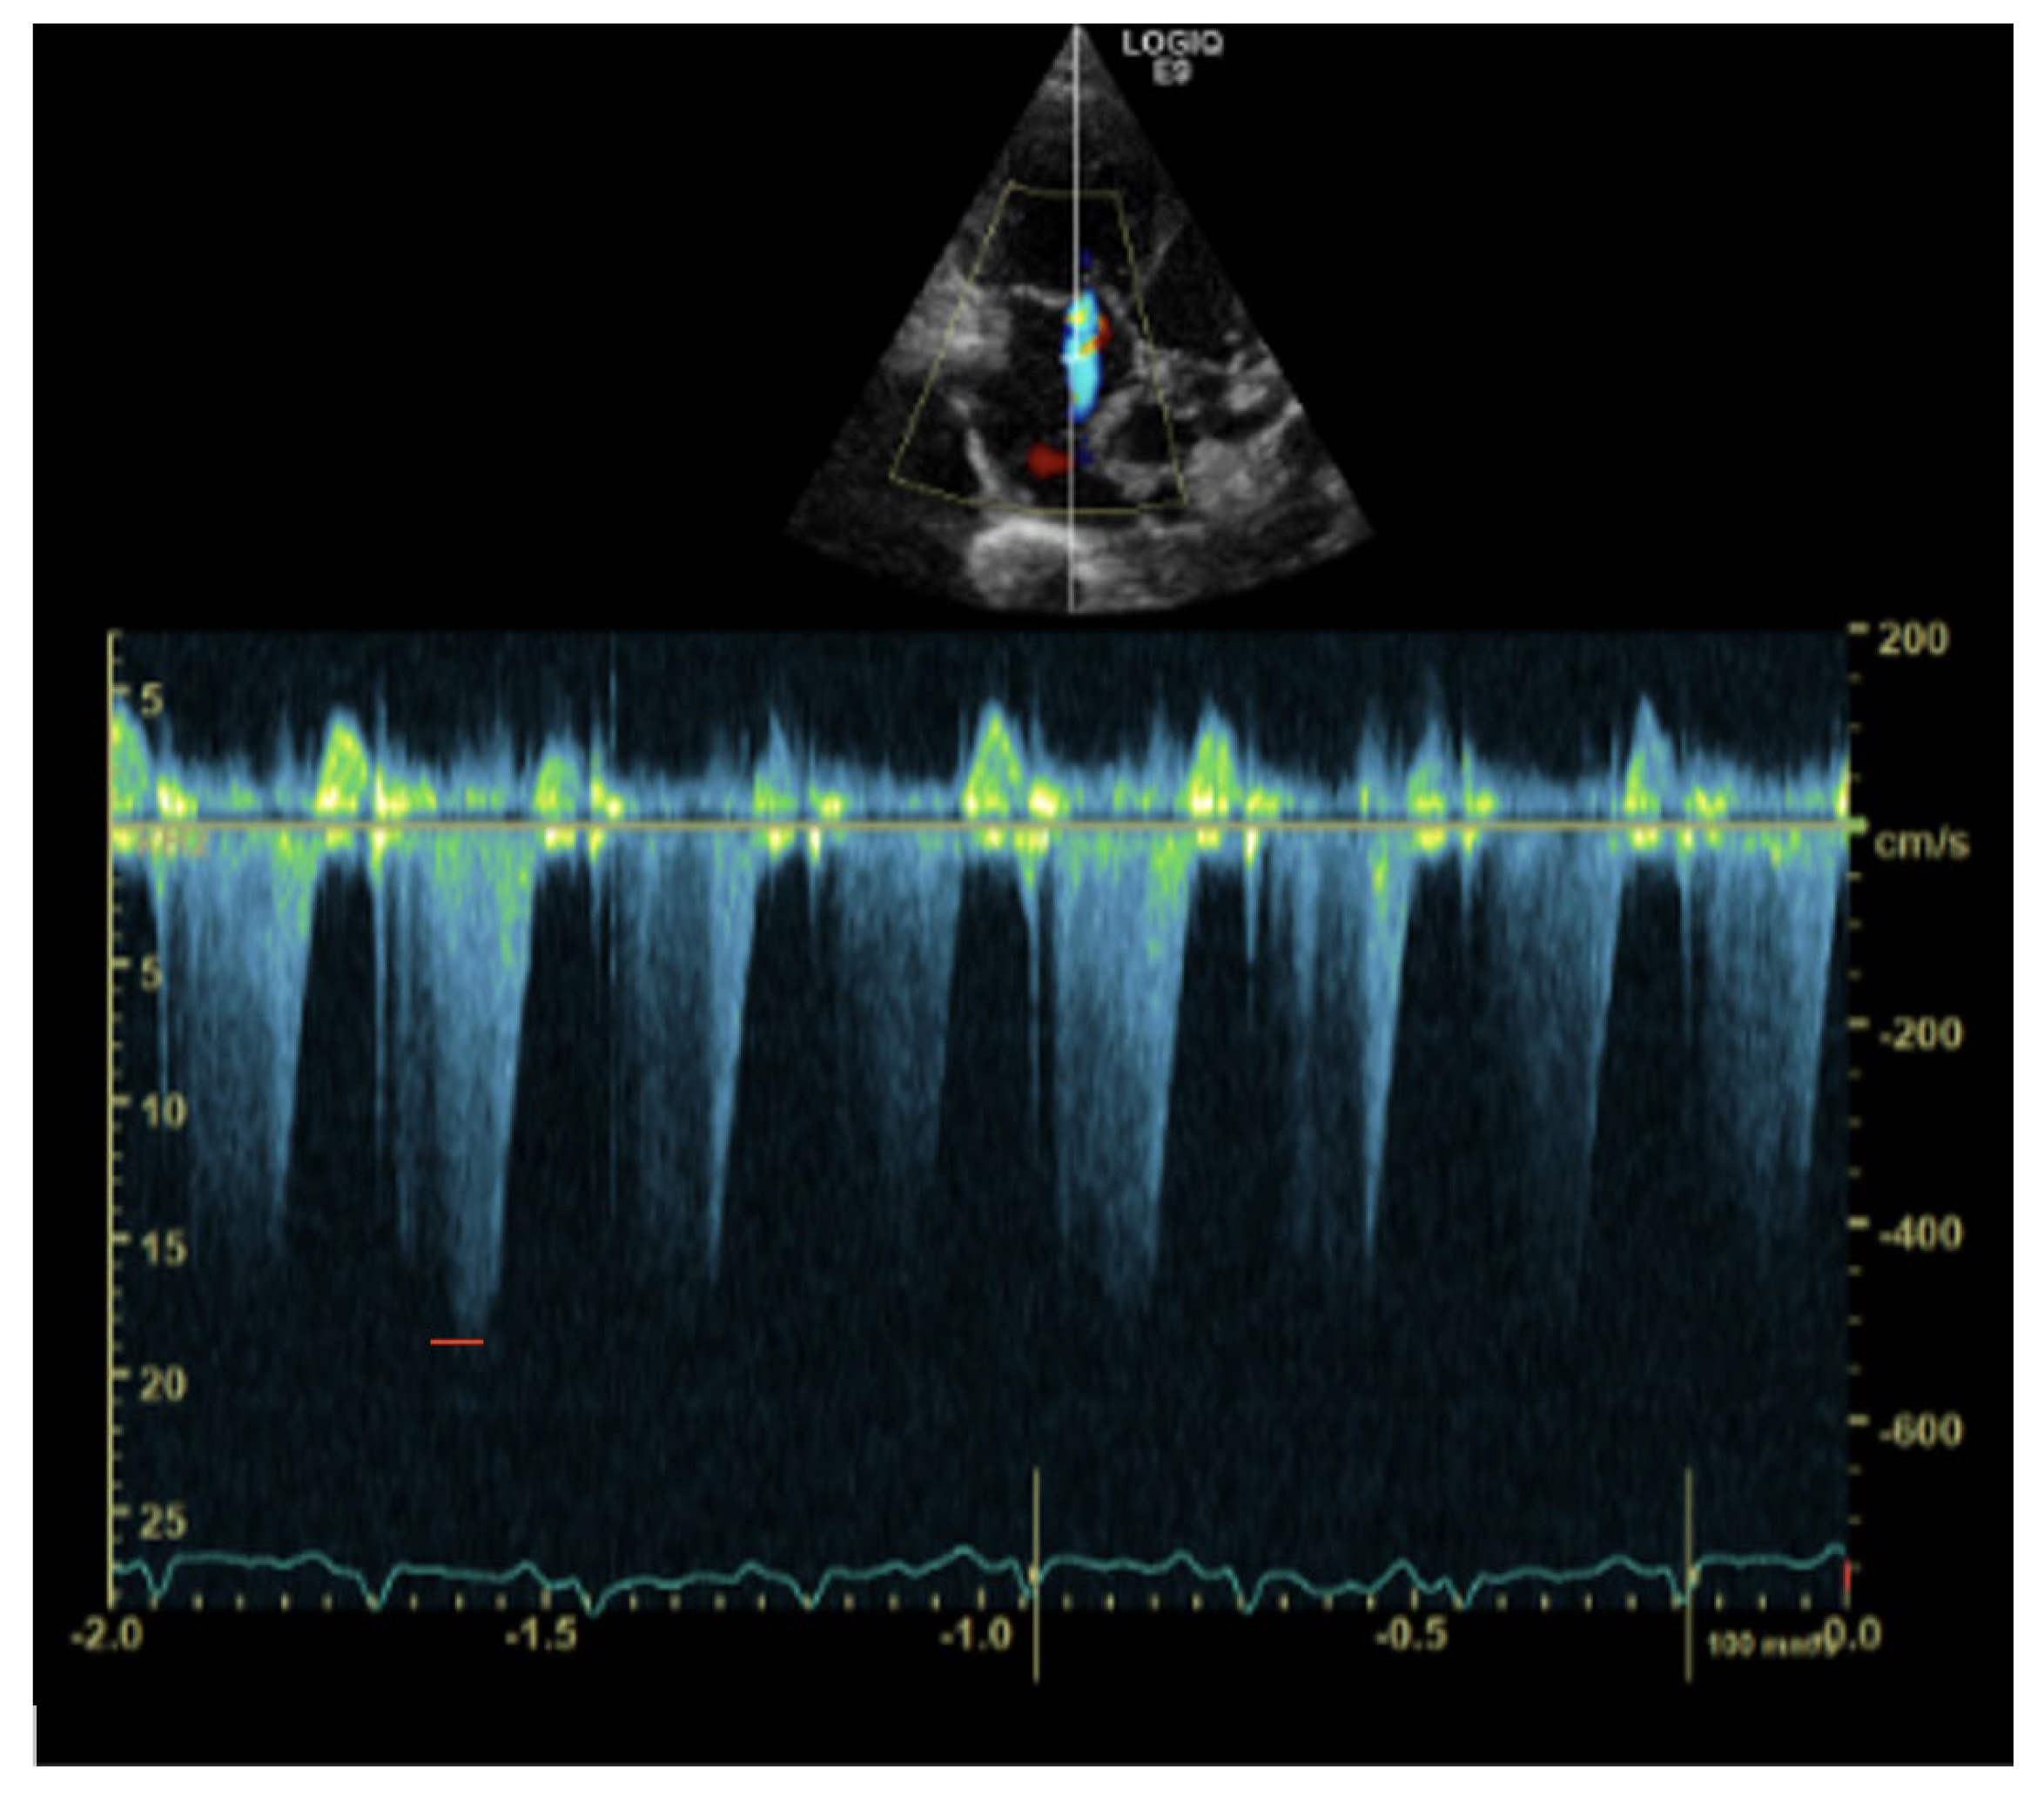

1. Case Description